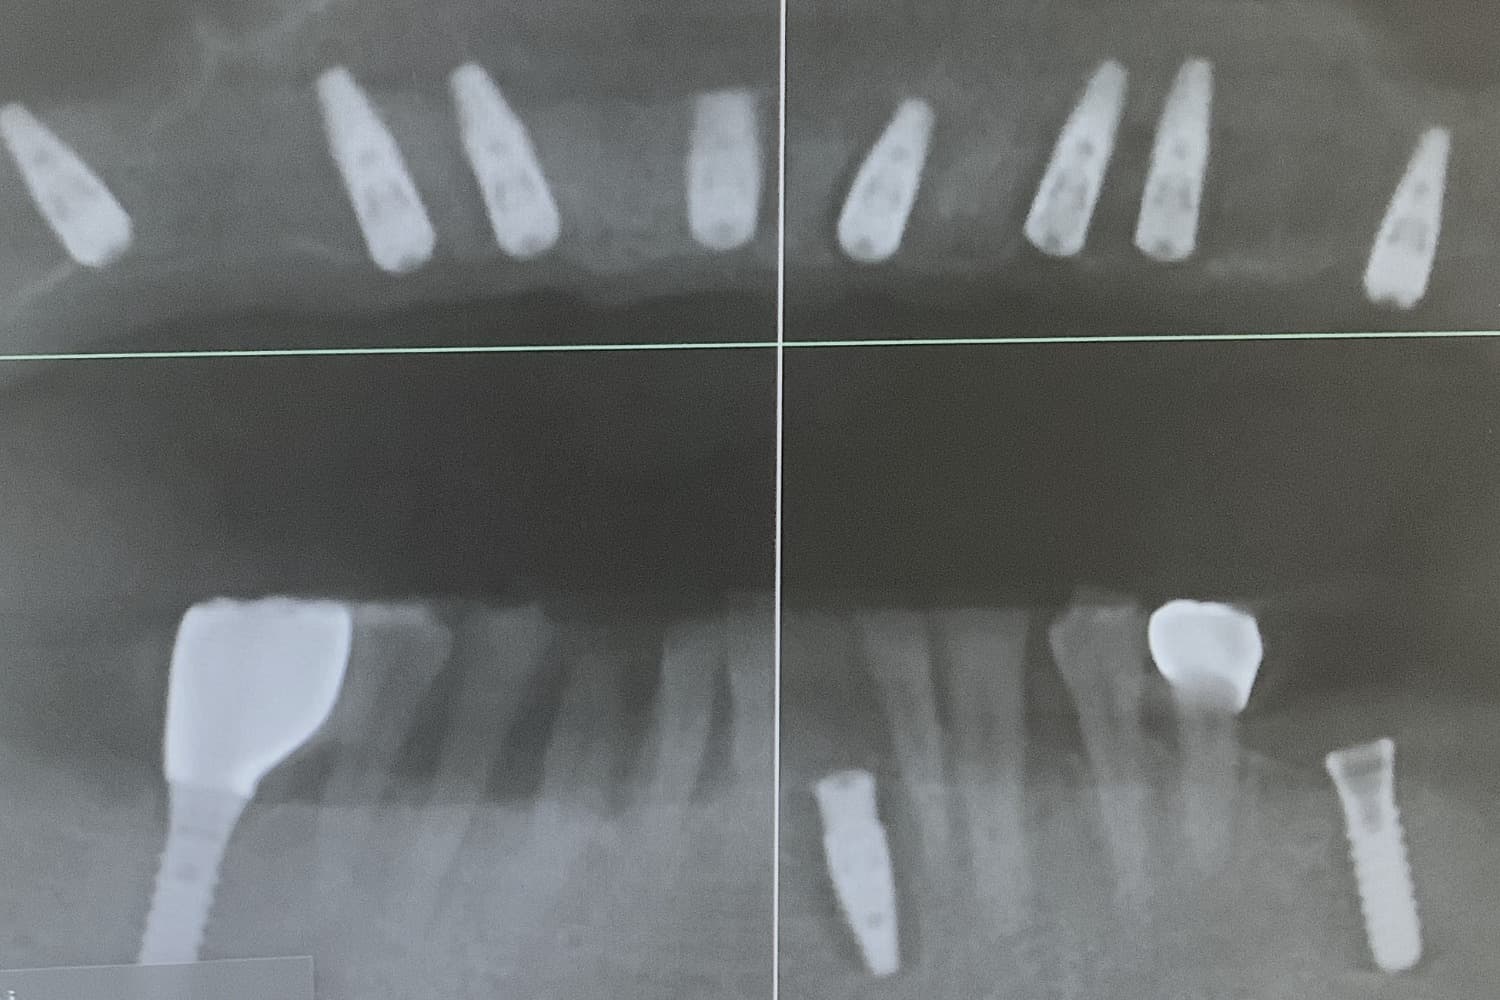

左下奥歯3本欠損部位のインプラント治療による修復

Before

左下奥歯3本の欠損部位をインプラント治療により修復をおこなう

年齢

40代

性別

女性

主訴

左下の歯がない箇所をインプラント治療したい

治療期間

4ヵ月

治療回数

5回

費用

825,000円

副作用・リスク

・骨の質や全身疾患によりインプラント体が骨と生着しない可能性がある ・術後に患部が腫れたり痛みが生じたりする可能性がある